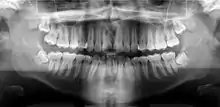

Panoramic radiograph

![]() A dental panoramic radiograph, showing the maxilla and mandible, all the teeth including the "wisdom teeth," the frontal and maxillary sinuses, the nasal cavity and the temporomandibular joint and other near by head and neck anatomy. | |

A panoramic radiograph is a panoramic scanning dental X-ray of the upper and lower jaw. It shows a two-dimensional view of a half-circle from ear to ear. Panoramic radiography is a form of focal plane tomography; thus, images of multiple planes are taken to make up the composite panoramic image, where the maxilla and mandible are in the focal trough and the structures that are superficial and deep to the trough are blurred.